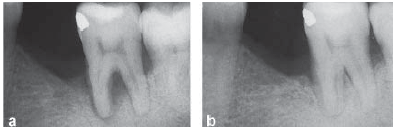

Figura 1

Aspecto radiográfico de um defeito na área de furca antes do

tratamento (a) e 6 meses após o tratamento (b).

Paciente apresenta-se com mobilidade dentária grau 2 no elemento 37. Uma área radiolúcida pode ser vista na radiografia (Fig. 1-a). À sondagem, não foi detectada bolsa periodontal na região de furca, apenas 6 mm no sítio distal e 5 mm no sítio mesial.